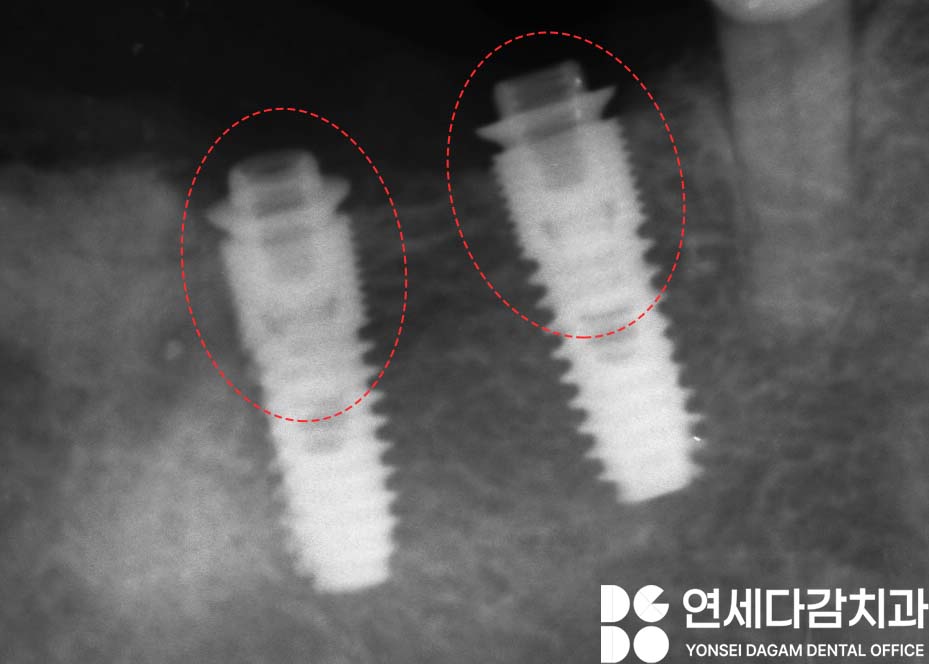

확인 결과 스크류가 하나 더 있는 것을

알 수 있었습니다.

내부 스크류까지 마저 제거하여,

SCRP 타입으로 바꿔

새롭게 제작하고자 합니다.